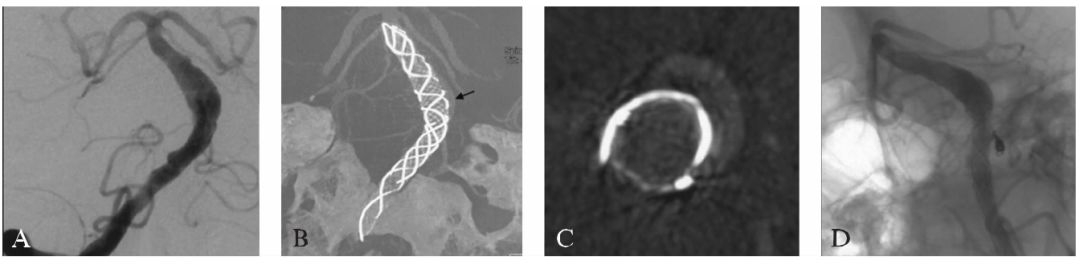

图16-1椎基底动脉冗长扩张症患者术前影像学检查

A:MRI平扫T₂WI轴位示基底动脉血管腔内血栓形成;

B:CTA三维成像(后前位观);

C:椎基底动脉冗长扩张症血管造影图像

7F导引导管超选至右侧椎动脉的C₁~C₂水平。使用双导管技术,由于基底动脉扩张段的管径明显大于支架管径,因此我们使用1枚Cosmos 10mm/36cm的弹簧圈在基底动脉扩张处释放但不解脱,从而辅助稳定另1根微导管释放支架(图16-2A)。使用多支架的Telescoping技术,植入2枚LEO支架重建动脉管腔(图16-2B),并在支架释放后撤出弹簧圈,Dyna CT示支架之间部分重叠覆盖(图16-2C)。术后患者症状减轻,第7天时症状完全消失。

图16-2患者首次介入治疗的过程及术后复查影像

A:在基底动脉膨胀部位暂时植入弹簧圈为支架作支撑;

B:使用Telescoping技术释放2枚LEO支架覆盖病变动脉,而后收回弹簧圈以减少局部血流动力学影响;

C:术后Dyna CT显示支架的形态(前后位观);

D:术后1个月CTA复查示病变瘤样扩张消失,管径与支架管径一致